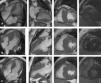

Cardiac magnetic resonance imaging (4-chamber, 2-chamber and short-axis cine and late gadolinium enhancement (LGE) views): (A, Case 1): asymmetric hypertrophic cardiomyopathy (HCM) with late gadolinium enhancement (LGE) in the hypertrophied segments; (B, Case 2): asymmetric HCM with LGE in the hinge points; (C, Case 3): asymmetric HCM with LGE in the hinge points.